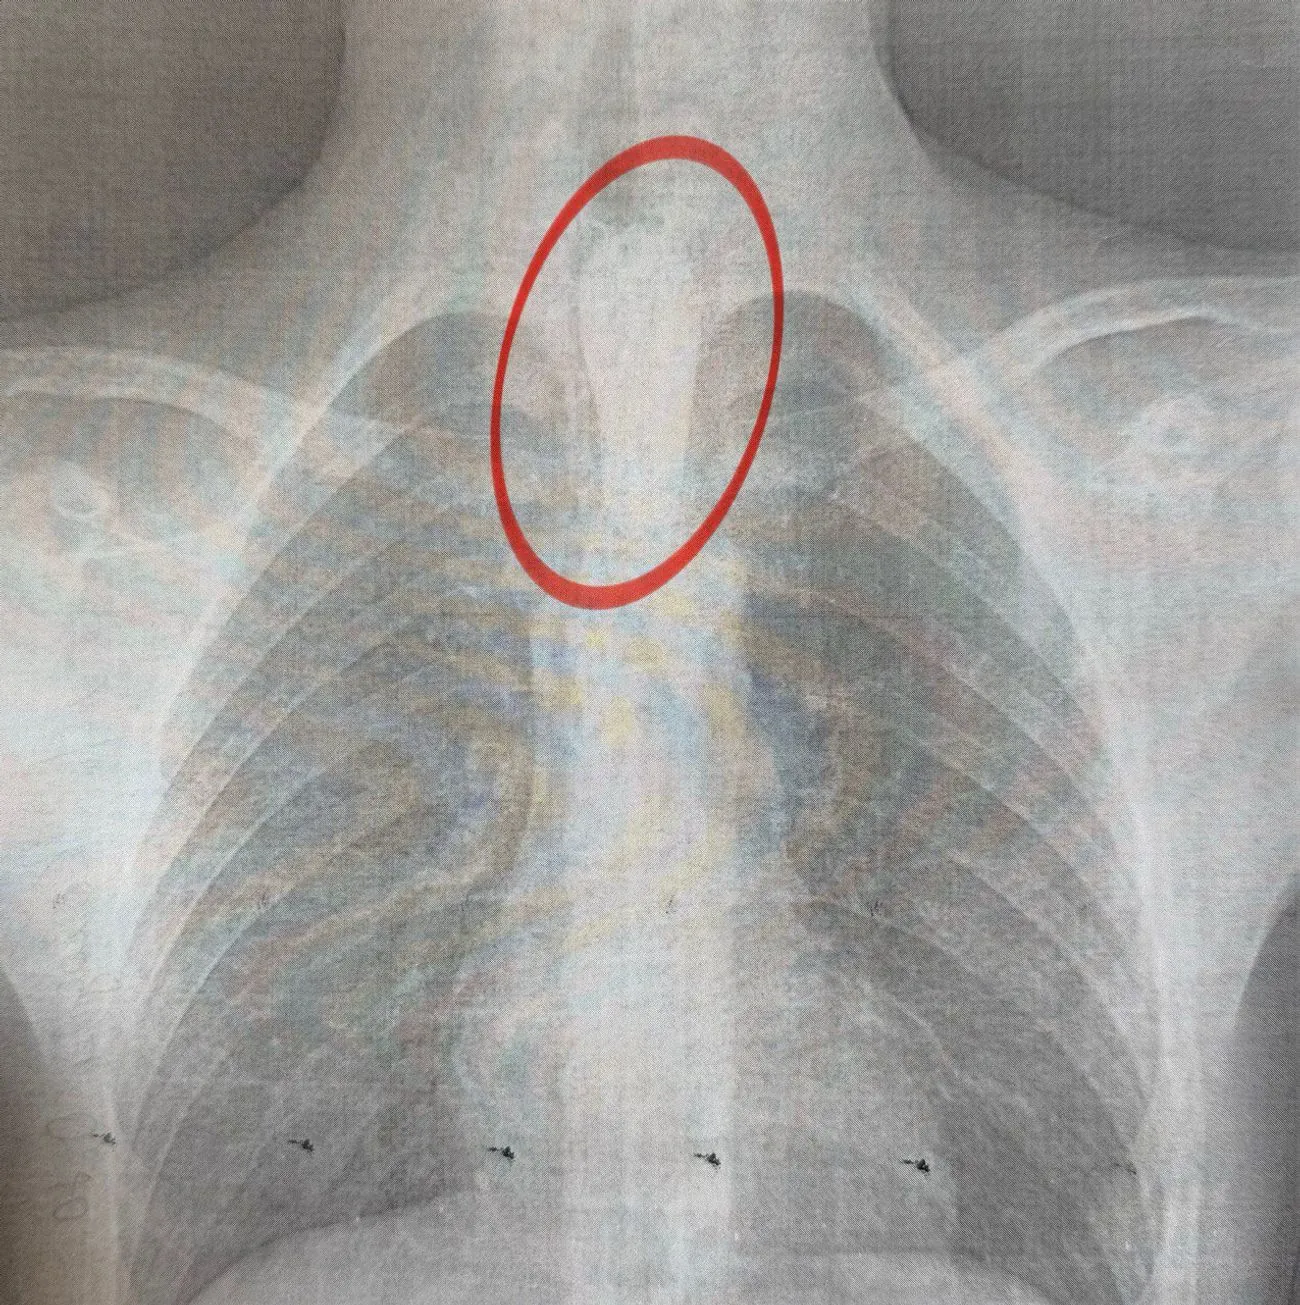

Медики пояснили, що стравохід має природні звуження на рівні шиї, біля аорти та на вході до шлунка. І у цьому випадку шматок їжі застряг якраз біля аорти, на другому звуження стравоходу. При цьому слина виробляється постійно, а проковтнути її неможливо. Крім того, через надмірну слинотечу порушується дихання.